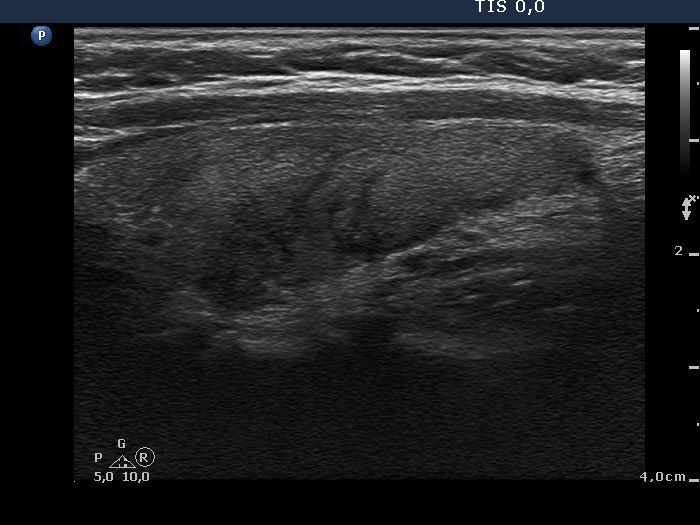

Subacute granulomatous thyroiditis - case 1790 (ultrasonographic picture 5)

Left lobe, longitudinal view.